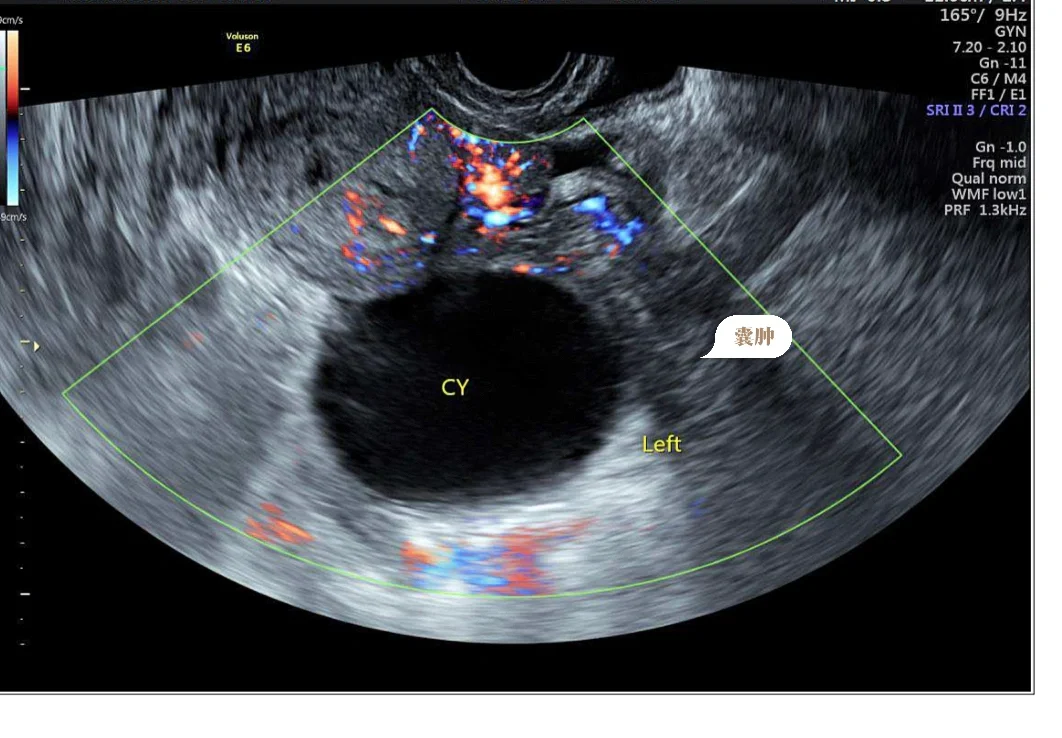

第一次孕检时(孕6周)发现左侧卵巢长了一个7cm左右的囊肿,大概是孕激素导致的一个生理性囊肿,因为两三个月前,备孕检查和体检的时候还一切正常。